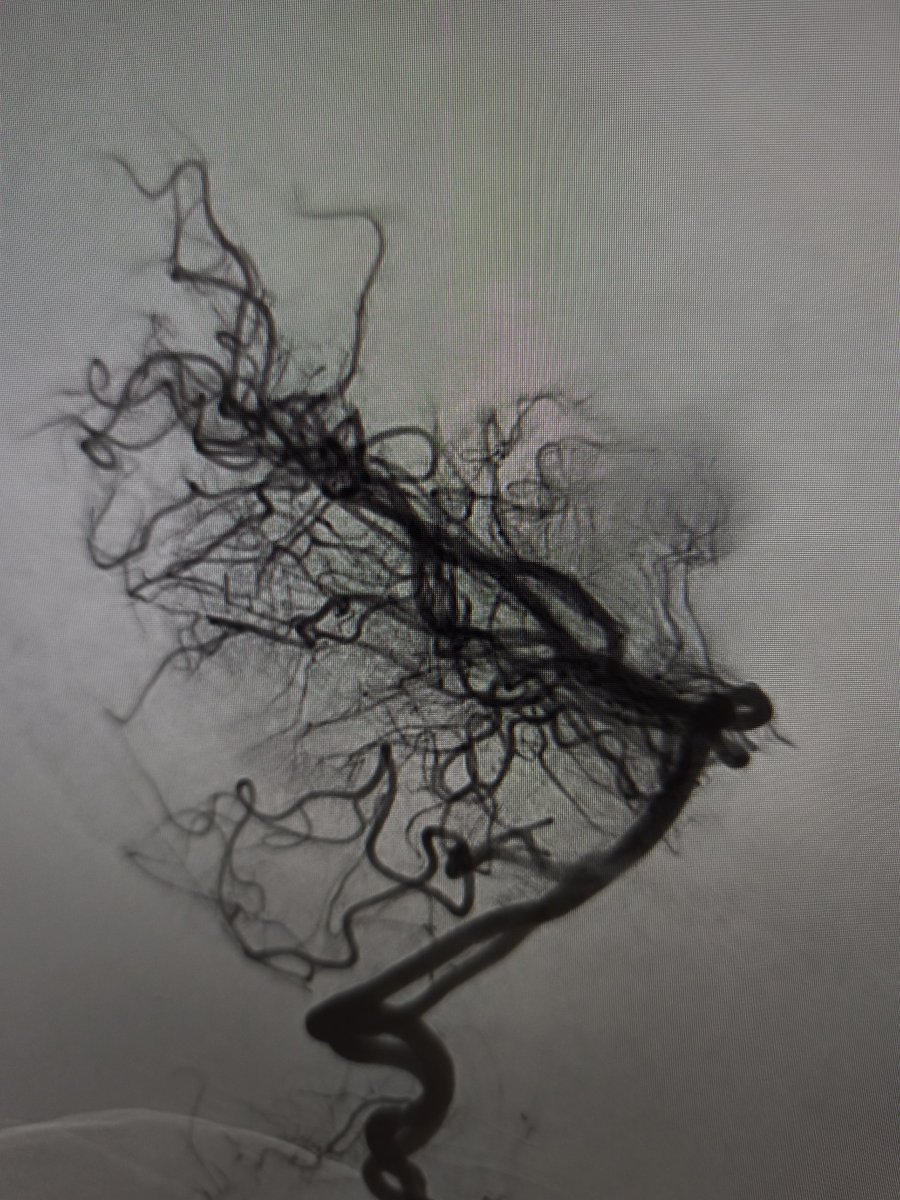

Ruptured cerebral arteriovenous malformation (#AVM), S&M grade IV

#Embolization + #Surgery

Complete Removal !!

Great team !!

Dr. Alberto Blanco (NSG)

Dr. Raquel Alcaraz (AN)

Dr. Raquel Tolos (AN)

Dr. Nerea Joshua (Neurophysiol)

@Sremollo

@IsaRCaamano

Rosa García-Sort (INR Nurse)